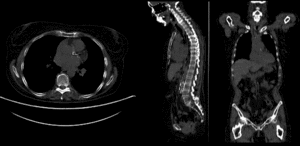

rigidrigid

affine alignmentaffine alignment

BSpline registration of full volumes. 9 x 9 x 5 gridBSpline registration of full volumes. 9 x 9 x 5 grid

BSpline registration of full volumes. 11 x 11 x 7 gridBSpline registration of full volumes. 11 x 11 x 7 grid